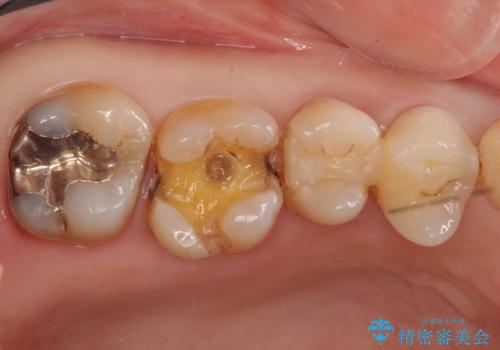

- 虫歯治療を希望して来院。

保険適用の銀色のつめもののやり替えを行いました。

- 30.8万円(右上4567 emaxプレスインレー 7万円x4本)費用は治療当時の料金となります

自由診療のインレーの歯型には、シリコンを使用しています。また、処置時には8倍の拡大鏡を用いて、精密に治療しております。